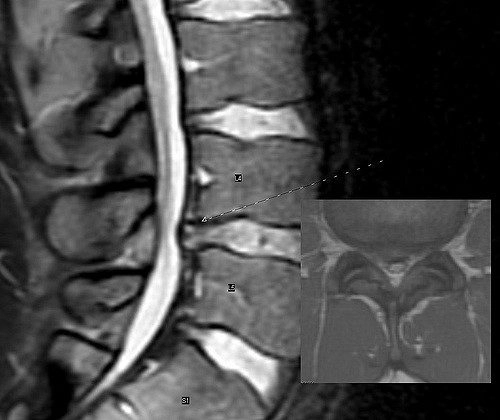

An x-ray imaging of a spine.

Your doctor or chiropractor will need to do a physical exam, followed by some questions about where and when the pain started.

Imaging tests will need to be taken to confirm if you have a bulging disc or a herniated disc. Common imaging could include an MRI, X-rays, or CT scans.

This combination of information will allow your chiropractor or doctor to make a diagnosis about the root cause of your low back pain.